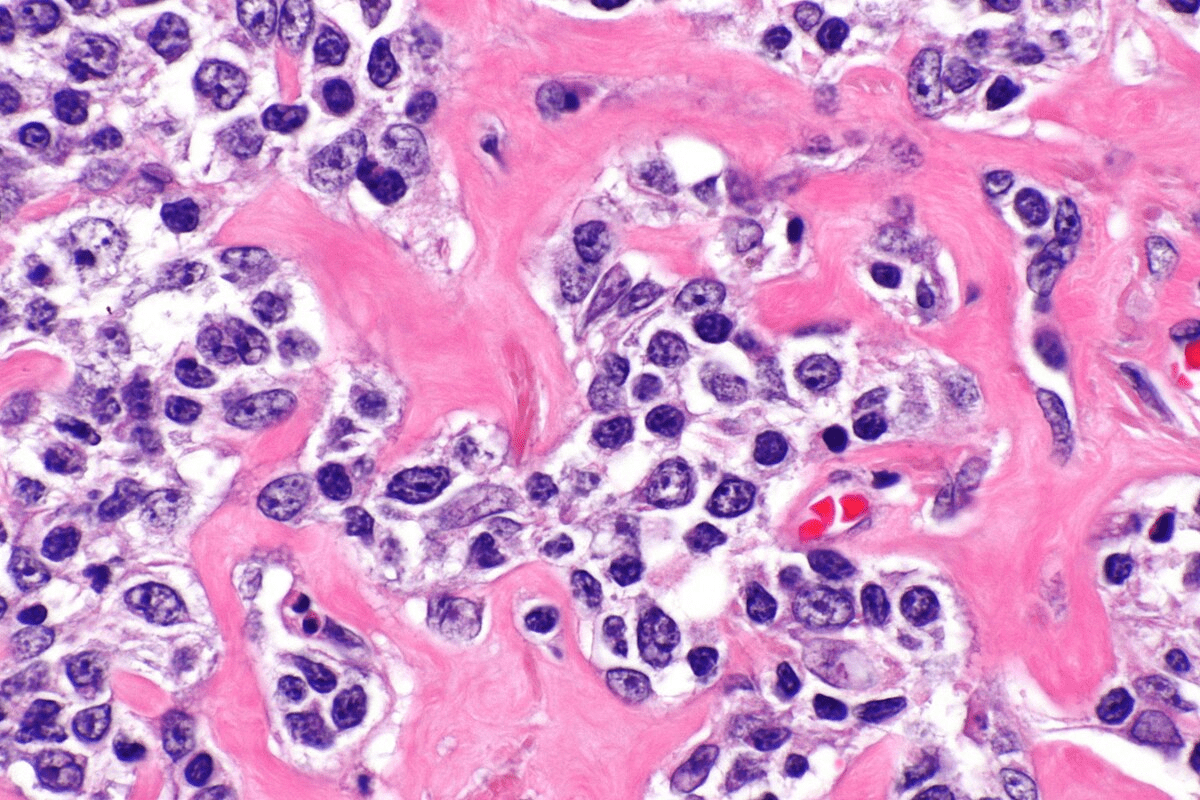

Sickle cell disease makes red blood cells misshapen and break down. Normally, red blood cells are flexible and round. But in sickle cell disease, they become rigid and sickle-shaped, leading to their premature destruction.